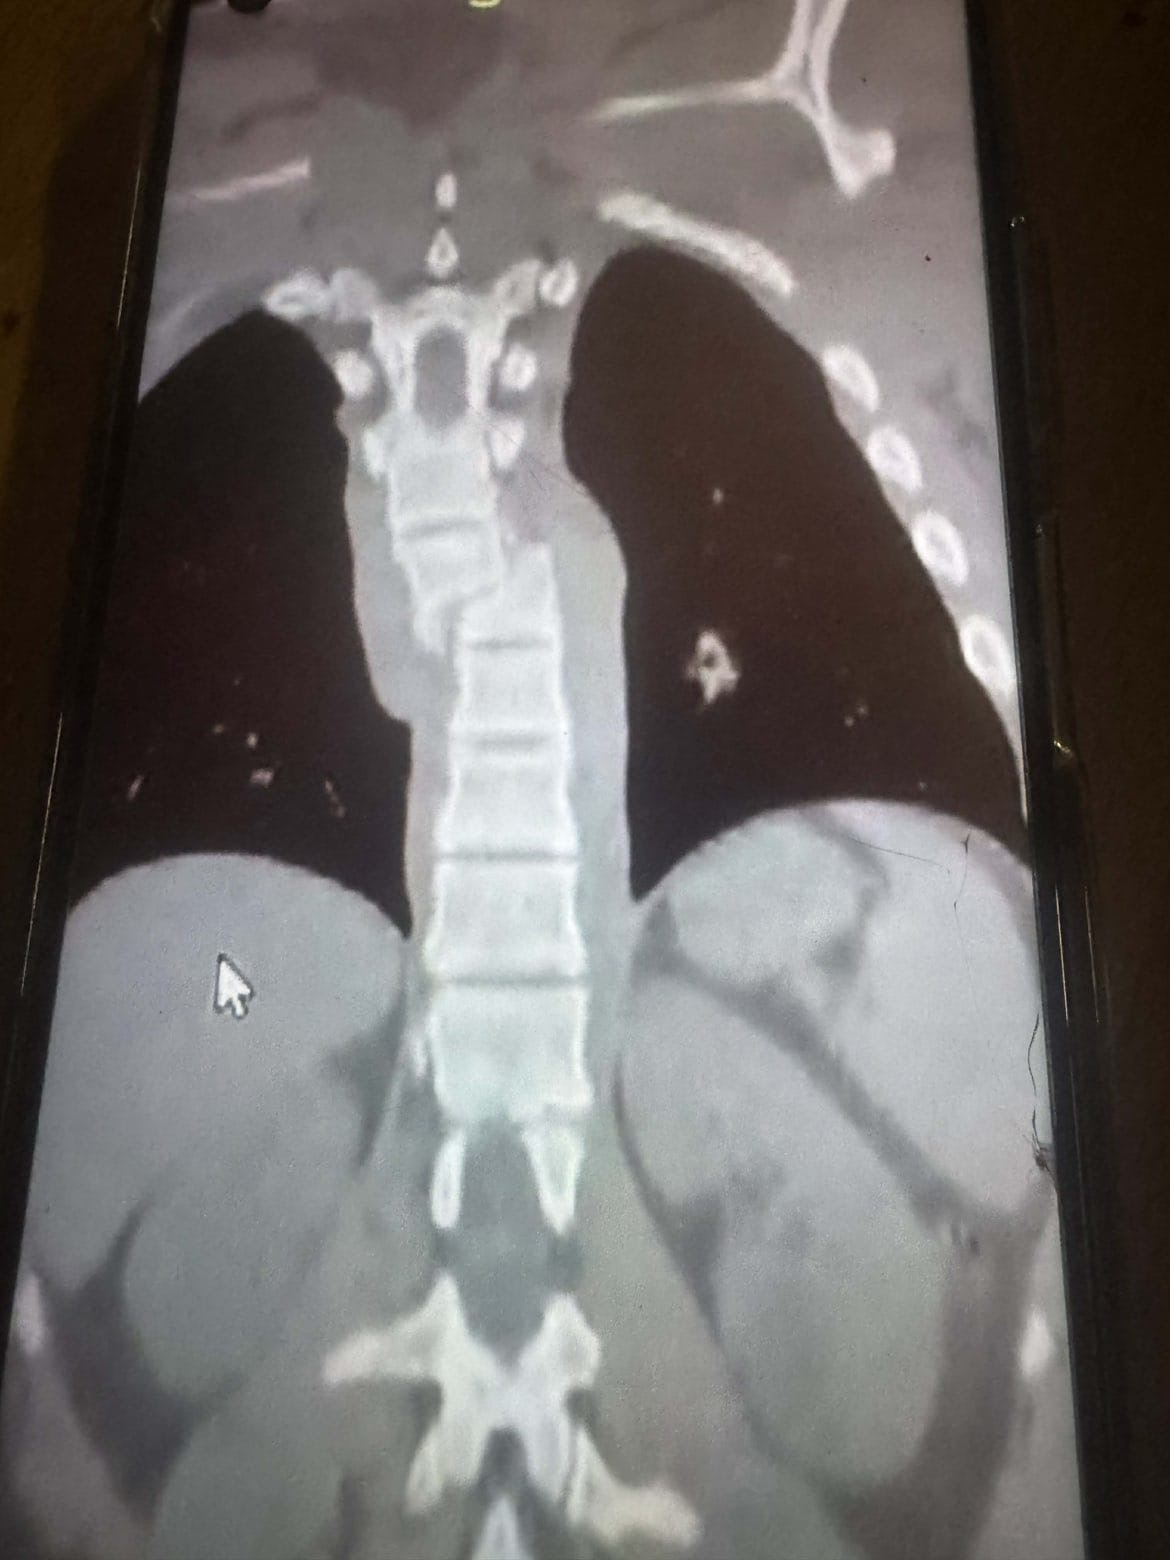

Am vergangenen Donnerstag hat ein einziger Moment alles verändert. Ensar hatte einen schweren Motorradunfall. Was danach folgte, war ein Albtraum für unsere ganze Familie. In Pristina konnte er nicht behandelt werden und musste dringend nach Skopje verlegt werden. Dort kämpften die Ärzte in einer sechsstündigen Notoperation um seine Wirbelsäule, die in der Mitte gebrochen war.

Zusätzlich erlitt er eine gebrochene Rippe und eine schwere Verletzung der Lunge. Durch ein Loch in der Lunge kam es zu weiteren Komplikationen. Seitdem liegt er auf der Intensivstation, sein Zustand ist kritisch und leider zuletzt eher schlechter als besser geworden.